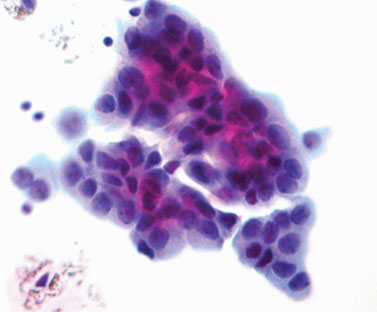

High-Grade Urothelial cell Ca.

Criteria [2]:

High N:C; hyperchromatic nuclei; coarsely granular chromatin; irregular nuclear outline; large nucleoli (occasionally)

- cells can have Melamed-Wolinska bodies and background can be necrotic

HG papillary urothelial CA: clusters of marked atypia c pleomorphic nuclei, coarse chromatin and prominent nucleoli. Cytoplasm can range from dense to vacuolated. Irreg nuclear contours and irreg coarse chromatin, nucleoli are frequently present